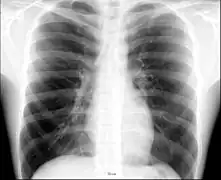

Radiografía de tórax

La radiografía de tórax, comúnmente llamada placa de tórax, es el examen de diagnóstico por rayos X más comúnmente realizado. Una radiografía de tórax genera imágenes del corazón, los pulmones, las vías respiratorias, los vasos sanguíneos y los huesos de la columna y el tórax.

Placa posteroanterior de tórax en el sujeto normal.

Placa lateral de tórax en el sujeto normal. El lado izquierdo del tórax se apoya sobre el cassette de la película radiográfica para impedir la magnificación del corazón. Las placas posteroanterior y lateral constituyen el "par radiográfico de tórax".- Radiografía torácica mostrando una prominente área de consolidación aérea cuneiforme en pulmón derecho, característica de la neumonía lobar aguda.